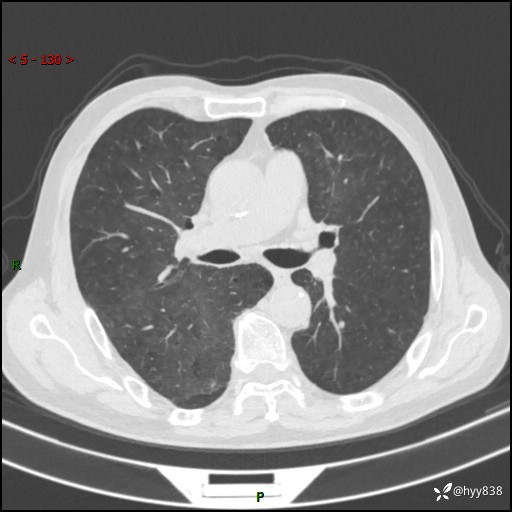

儿女怕老人寂寞,养了两只鹦鹉,呼吸科主任问我典不典型---结果公布~

武医生 等 4 位达人已点赞患者性别:男

患者年龄:71岁

主诉:喘气半年余,咳嗽乏力伴味觉减退2月余

简要病史:者半年前左右无明显诱因出现呼吸困难,轻微运动后出现喘气,未予以重视。2月余前受凉感冒后出现咳嗽,咳白色泡沫痰,不易咳出,于当地医院行输液治疗,未见明显好转,并感觉全身乏力,体力下降,并感口苦,味觉减退。近10余天前感咳嗽喘气加重,咳白色泡沫痰,不易咳出,口苦,味觉减退加重。为进一步检查及治疗,入我院就诊,门诊以“呼吸困难”收入院治疗。 起病以来,患者精神,睡眠,饮食欠佳,大小便可,体力下降明显,体重稍下降。

辅助检查:CT

临床诊断:呼吸困难

讨论:诊断?

胸部CT平扫